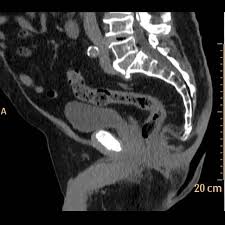

La risonanza magnetica addome e pelvi analizza lo stato di salute degli organi pelvici della donna per individuare eventuale endometriosi, cure e terapie.

L'endometriosi colpisce 3 milioni di donne solo in italia. La risonanza magnetica pelvi è lo studio degli organi e delle strutture contenute nella pelvi (bacino) tramite metodica di risonanza magnetica.per effettuare la risonanza magnetica. La risonanza magnetica è una tecnica di imaging che serve ad indagare diversi organi e tessuti molli.

La risonanza magnetica pelvica, inoltre, è spesso impiegata nella valutazione di reperti riscontrati in altre indagini (più frequentemente ecografia), per lo studio delle patologie tumorali, infiammatorie nonché malformative; La risonanza magnetica (rm) è una procedura non invasiva che fornisce immagini del corpo secondo qualsiasi piano, con dettaglio e contrasto ancora superiori a quelli della tc ma senza impiegare i raggi x. Se decidete di affrettare il vostro iter medico e sottoporvi ad una risonanza magnetica presso uno studio.

L'endometriosi colpisce più del 5% delle donne, ed è causa di dolore pelvico e infertilità nel 50% dei casi. La risonanza magnetica pelvica, inoltre, è spesso impiegata nella valutazione di reperti riscontrati in altre indagini (più frequentemente ecografia), per lo studio delle patologie tumorali, infiammatorie nonché malformative; La risonanza magnetica (rm) è una procedura non invasiva che fornisce immagini del corpo secondo qualsiasi piano, con dettaglio e contrasto ancora superiori a quelli della tc ma senza impiegare i raggi x.

Nella donna trova inoltre impiego nello studio dell'endometriosi e, più in. Normale aspetto della parete muscolare pelvica anteriore. Risonanza magnetica addome inferiore e scavo pelvico (endometriosi).